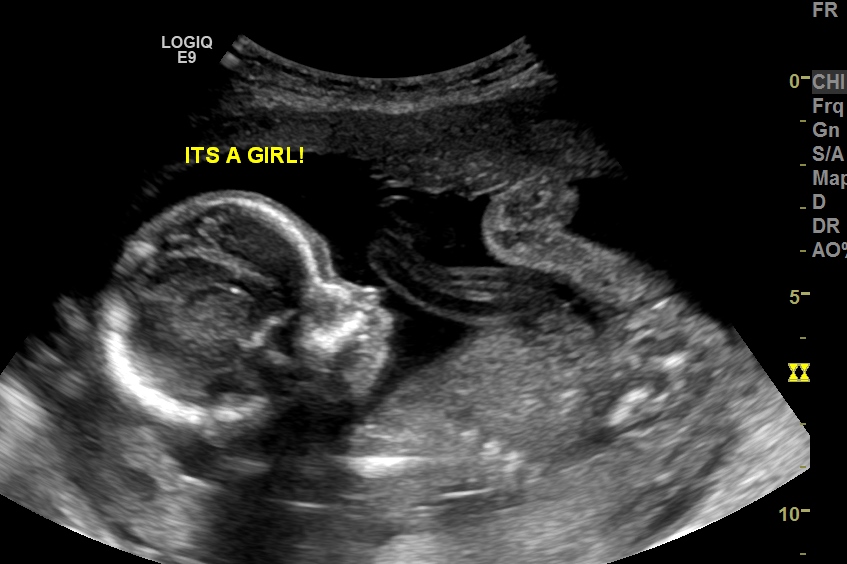

We are still in shock don't think I will believe it till I hold her. Please give me your honest opinions what do you think? After 3 boys I am so excited yet need some reasurance. Thank you for your time.

Attachment 31099